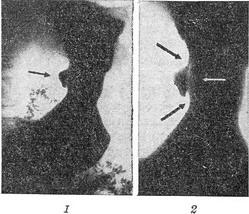

До рентгеноморфологическим ознаками відносяться ніша (рис. 1,1), вал навколо ніші (рис. 1,2) і конвергенція складок (рис. 2). Симптом ніші є прямим відображенням виразки і тому має найбільше діагностичне значення. Виявлення ніші в значній мірі залежить від розмірів, форми і локалізації виразки. Важко діагностуються плоскі, поверхневі виразки. Глибока виразка невеликого діаметра також іноді не виявляється у силу того, що вхід до неї може бути закритий набряклими оточуючими тканинами. Відносно легко виявляються виразки цибулини дванадцятипалої кишки та малої кривизни шлунка (найчастіша локалізація). Важче виявляються виразки антрального відділу і внелуковічние виразки дванадцятипалої кишки і особливо важко субкардиальные виразки і виразки великої кривизни шлунка. В нормальних умовах в силу косого розташування складок в цих відділах часто утворюється виражена зубчатость, на тлі якої важко виявити виразкову нішу.

Рис. 1. Виразка шлунка: 1 - виразкова ніша на контурі малої кривизни (вказана стрілкою); 2 - вал навколо ніші у вигляді світлого обідка в гирлі виразки.

Виразкова ніша, як правило, оточена більш або менш вираженим валом, морфологічним субстратом якого є набряк тканин, що оточують рану, ретракція слизової оболонки внаслідок скорочення мускулатури шлунка [Берг (Н. Н. Berg), Форсселль (G. Forssell)] і розвиток сполучної тканини. В прямій проекції вал має вигляд світлого обідка навколо ніші, зовнішні обриси якого нечіткі, поступово переходять у рельєф навколишньої слизової оболонки. Якщо вдається вивести нішу на контур, виходить профільне зображення валу. При цьому по обидві сторони від ніші виявляються симетричні дефекти наповнення. Досліджуючи суспензією барію не дуже густої консистенції і використовуючи жорстке випромінювання (100-125 кВ), можна отримати зображення вала на всю ширину перешийка виразки. У цьому випадку вал виглядає у вигляді світлого обідка в гирлі виразки (рис. 1, 2), ширина якого варіює в залежності від ступеня набряку країв виразки і вираженості склеротичного процесу. У цьому широкому світлому обідку іноді простежується ще одна більш тонка смужка - так звана лінія Хемптона, яку вважають відображенням скоротилася слизової оболонки. Поява лінії Хемптона в процесі лікування розцінюють як сприятливий прогностичний ознака, що вказує на зменшення запальної інфільтрації і набряку навколишніх тканин.